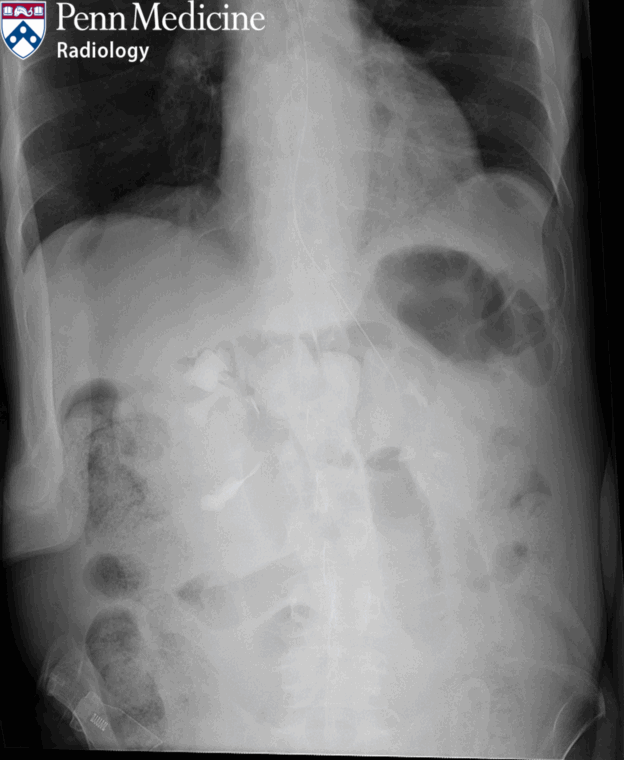

77-year-old man with abdominal pain and vomiting

A 77-year-old man with a history of HIV infection and COPD presented to the emergency department for abdominal pain and vomiting.